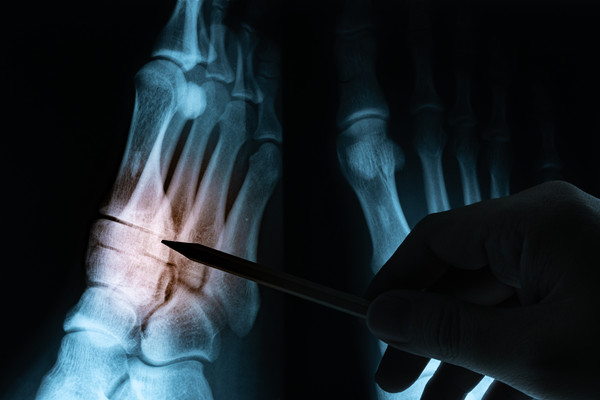

在门诊处经常见到有骨结核复发的朋友来再次就医,再次复发多是抗痨药使用不规范,以及骨质破坏严重,导致毒凝热结,使局部微循环障碍、血供不良所致缠绵难愈。今天关于骨结核复发怎么治疗,我们则来重点看一下采取靶位体液更新疗法的作用。